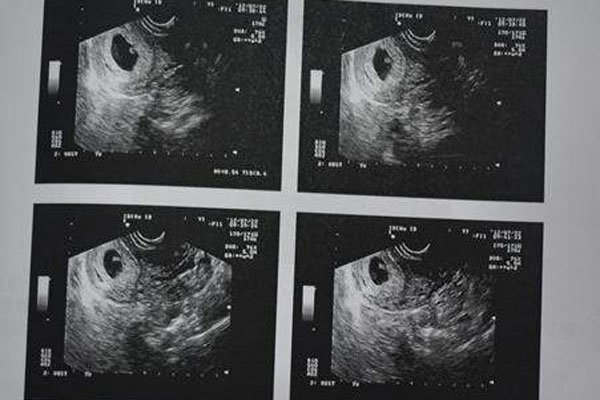

但是如果孕妇出血一直都是鲜红色的,那么一定要注意了,会发生这种情况一般是因为怀孕初期胚胎着床不稳定,出现这种情况并不代表是流产,只能说流产的几率比较大。第二种可能性是宫外孕,孕妇在6-7周时,用超声波还未看到胚胎,但是却有出血的症状,并且人类绒毛膜激素偏高时,这很可能就是宫外孕的情况,孕妈妈要注意伴随出血的同时是否有下腹疼痛的情况发生,有的话要立即就医。